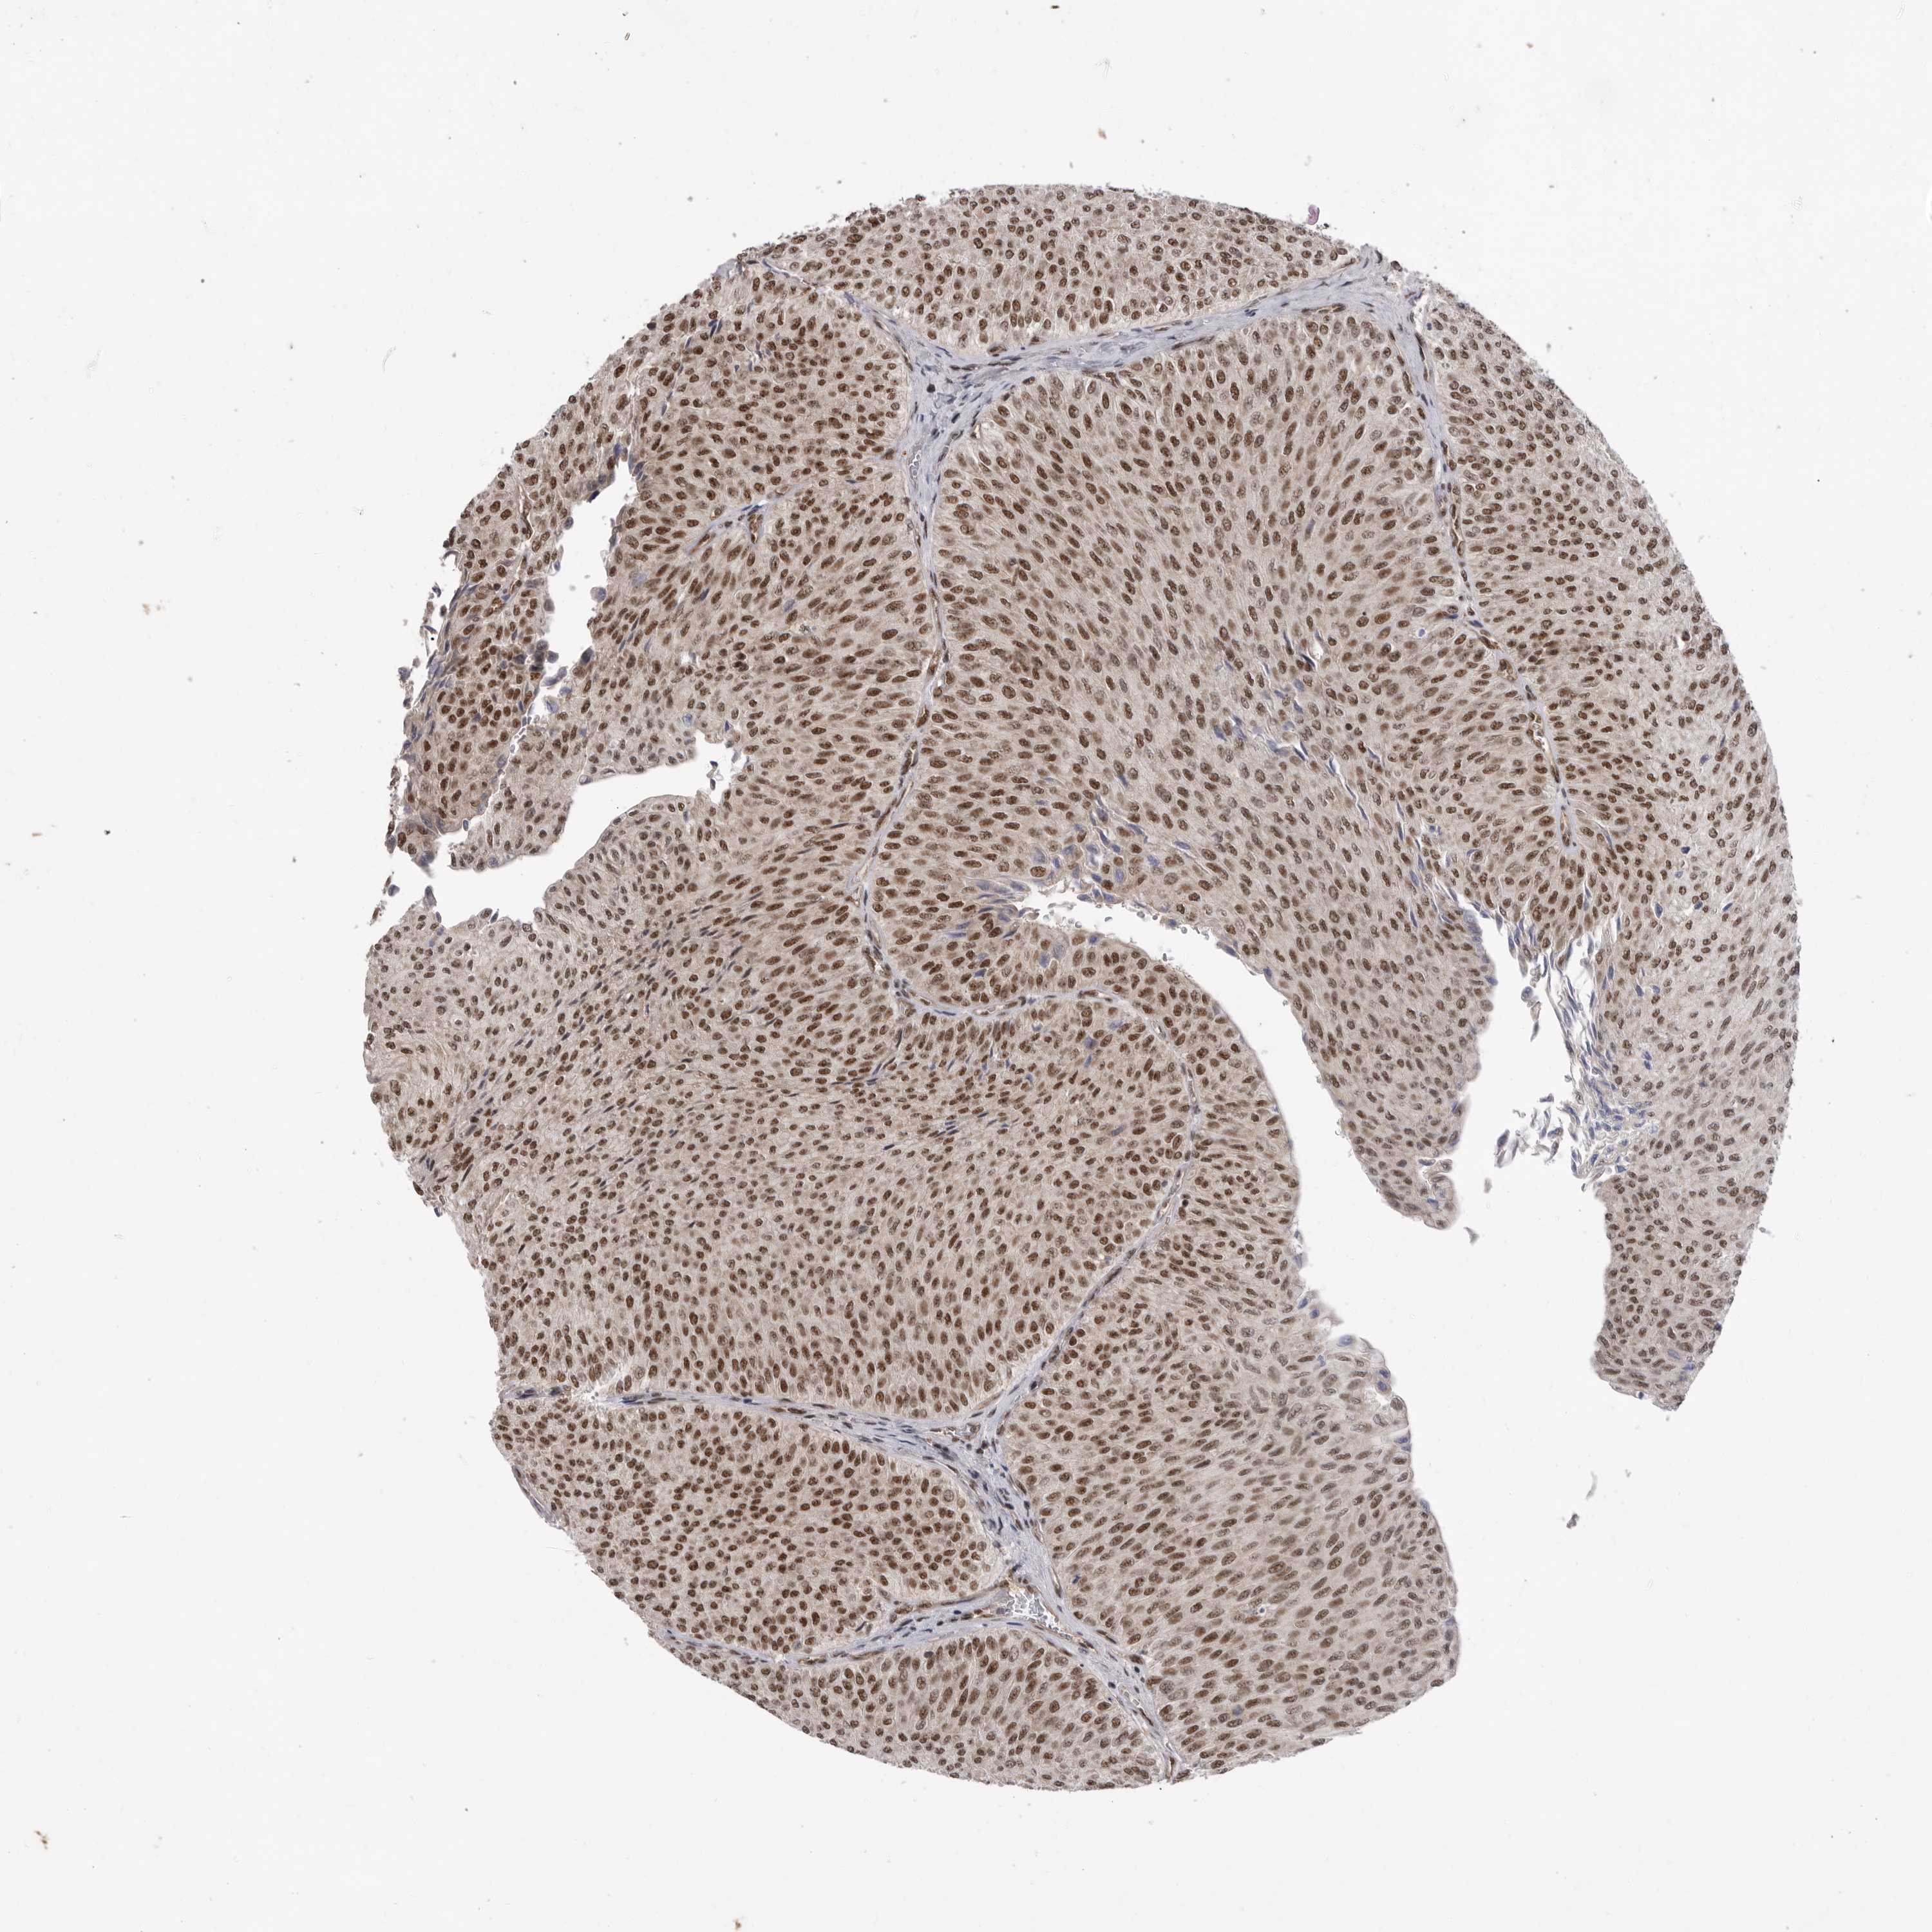

UROTHELIAL CANCER - Protein expressioni

A mouse-over function shows sample information and annotation data. Click on an image to view it in a full screen mode. Samples can be filtered based on level of antibody staining by selecting one or several of the following categories: high, medium, low and not detected. The assay and annotation is described here.

Note that samples used for immunohistochemistry by the Human Protein Atlas do not correspond to samples in the TCGA dataset.

Antibody stainingi

Antibody staining in the annotated cell types in the current human tissue is reported as not detected, low, medium, or high, based on conventional immunohistochemistry profiling in selected tissues. This score is based on the combination of the staining intensity and fraction of stained cells.

Each image is clickable and will lead to virtual microscopy that enables deeper exploration of all samples and also displays staining intensity scores, fraction scores and subcellular localization as well as patient and tissue information for each sample.

Antibody HPA027406

Antibody HPA027417

Antibody HPA027452

Staining

High

Medium

Low

Not detected

Intensity

Strong

Moderate

Weak

Negative

Quantity

>75%

75%-25%

<25%

None

Location

Nuclear

Cytoplasmic/membranous

Cytoplasmic/membranous,nuclear

Urothelial carcinoma, Low grade

Urothelial carcinoma, High grade